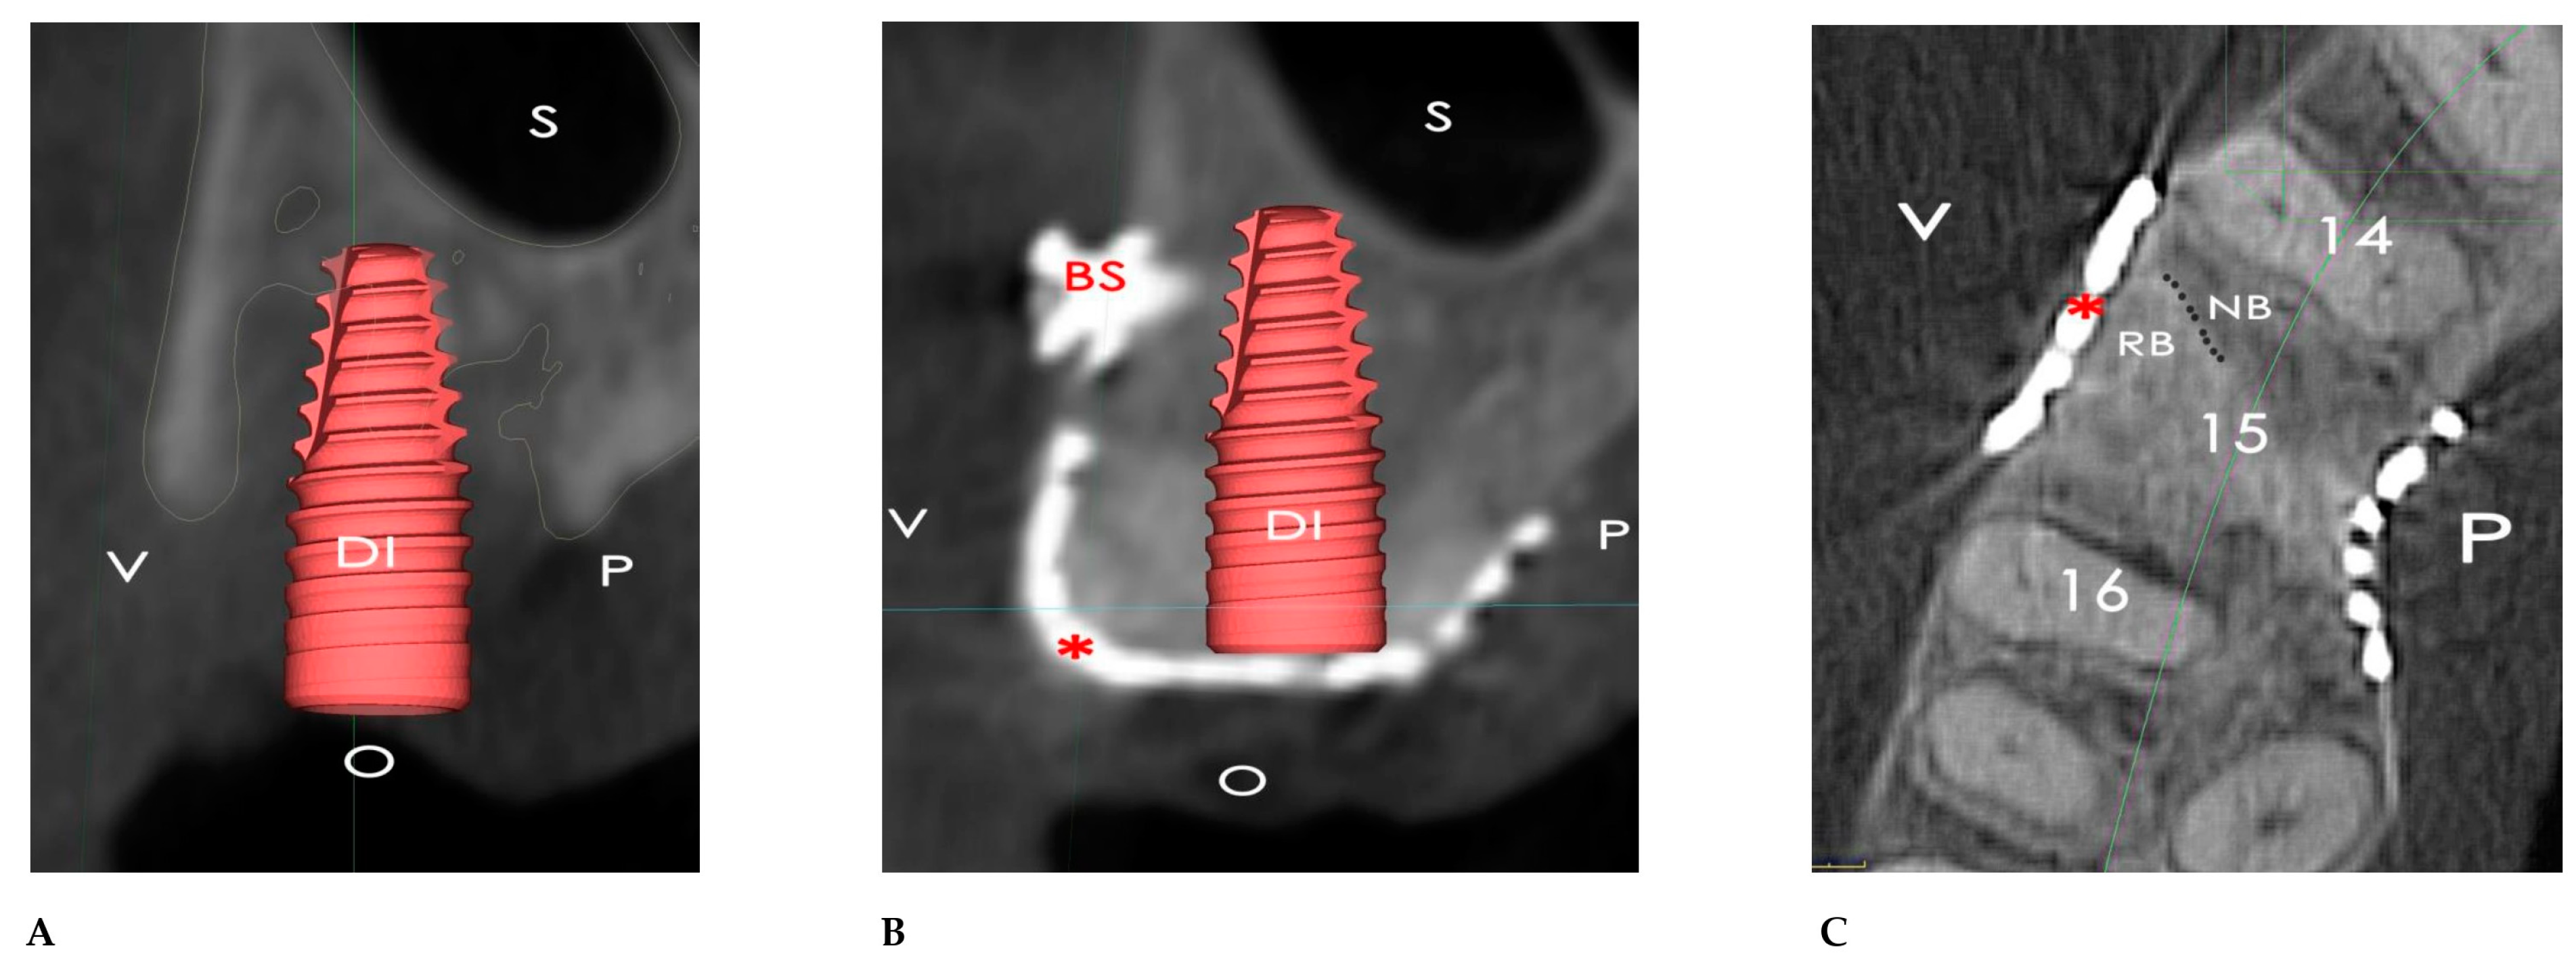

2.1. Surgical Simulation

2.2. GBR Simulation and Mesh Design